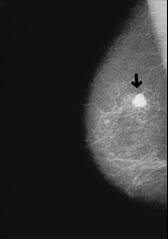

Breast cancer

Organism of blood group AB is vulnerable for most types of cancer like blood group A: all types of cancer which have cells behaving like cells of blood group A. See: Cancer according to blood groups.

Vulnerability for cancer with blood group AB like blood group A

Organism of blood group AB is as vulnerable for cancer like the organism of blood group A (4 Strategien, p.187).